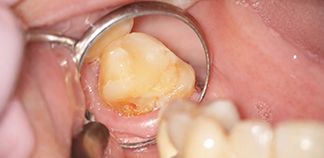

Результаты лечения пациентов

До лечения

Жалобы на длительную непрерывную боль ноющего характера.

Пациенту 45 лет.

Как лечили

Проведено перелечивание корневых каналов. Зафиксирована коронка на зуб.

Лечащие врачи

ЗАВОДОВ Олег Игоревич, ЯСАКОВА Мария Сергеевна